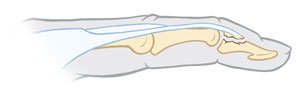

Greenstick fracture

The bone bends, but it may not break all the way. This happens most often in children, whose bones are softer and still growing.